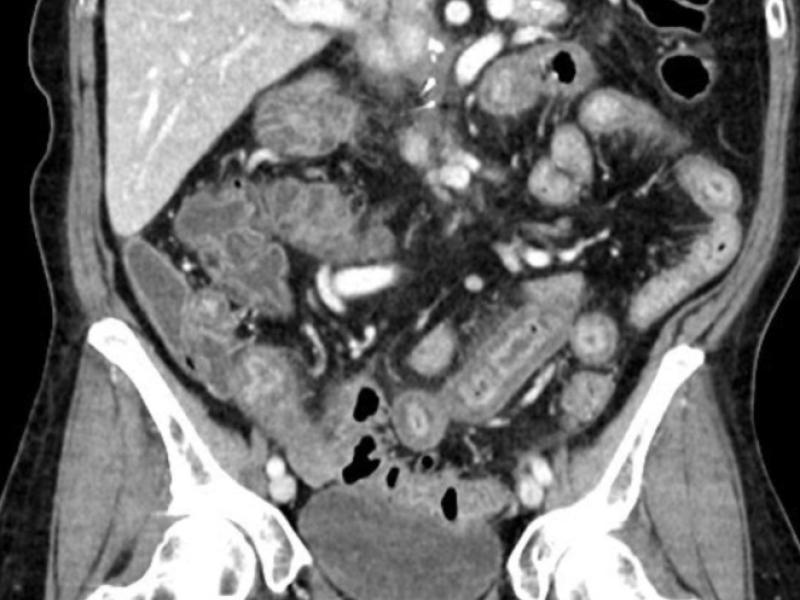

What's the diagnosis? By Dr. Abby Renko

A 50 yo female with a history of pancreatic cancer, on